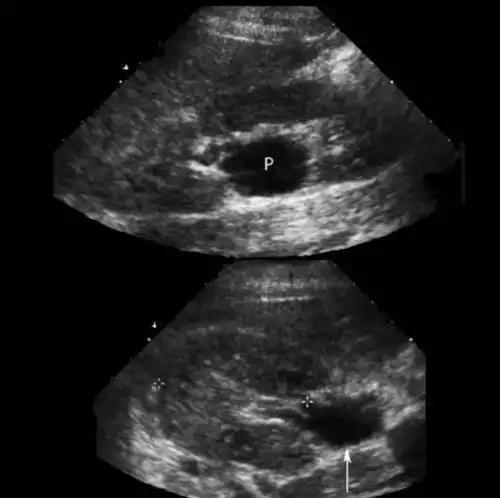

家里人带着她四处求医问药,彩超拍了一张又一张,就是查不出个明确的病灶。

但在极其隐秘的角落里,死死嵌着当年没取干净的残余避孕环碎片!